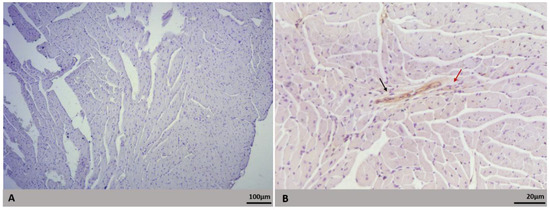

| Heart | Inflammatory infiltrate | 7/10 (70) | 9/10 (90) | 17/20 (85) |

| Cytoplasmic rarefaction | 7/10 (70) | 4/10 (40) | 11/20 (55) | |

| Increased cellularity | 2/10 (20) | 4/10 (40) | 6/20 (30) | |